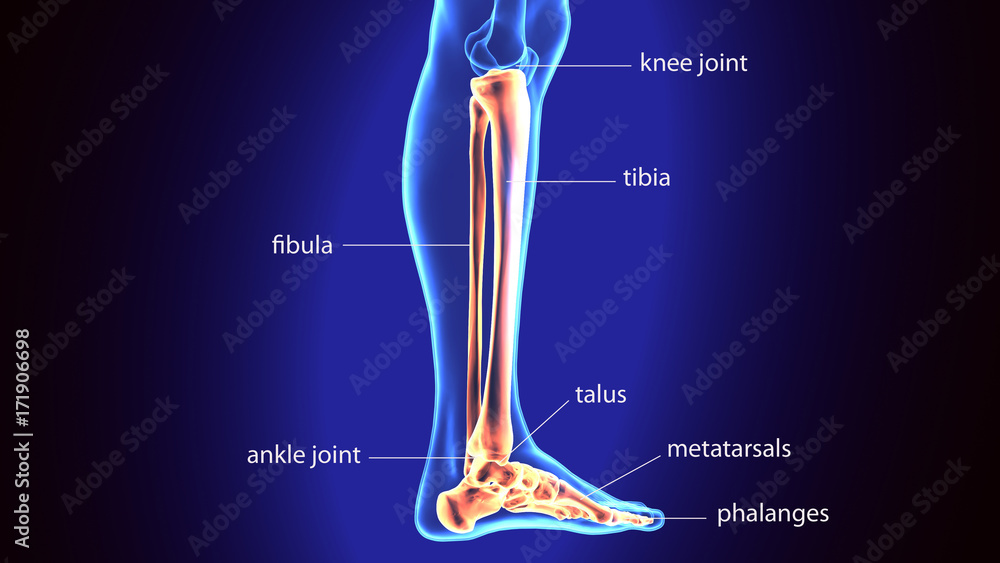

Curved tibia fibula